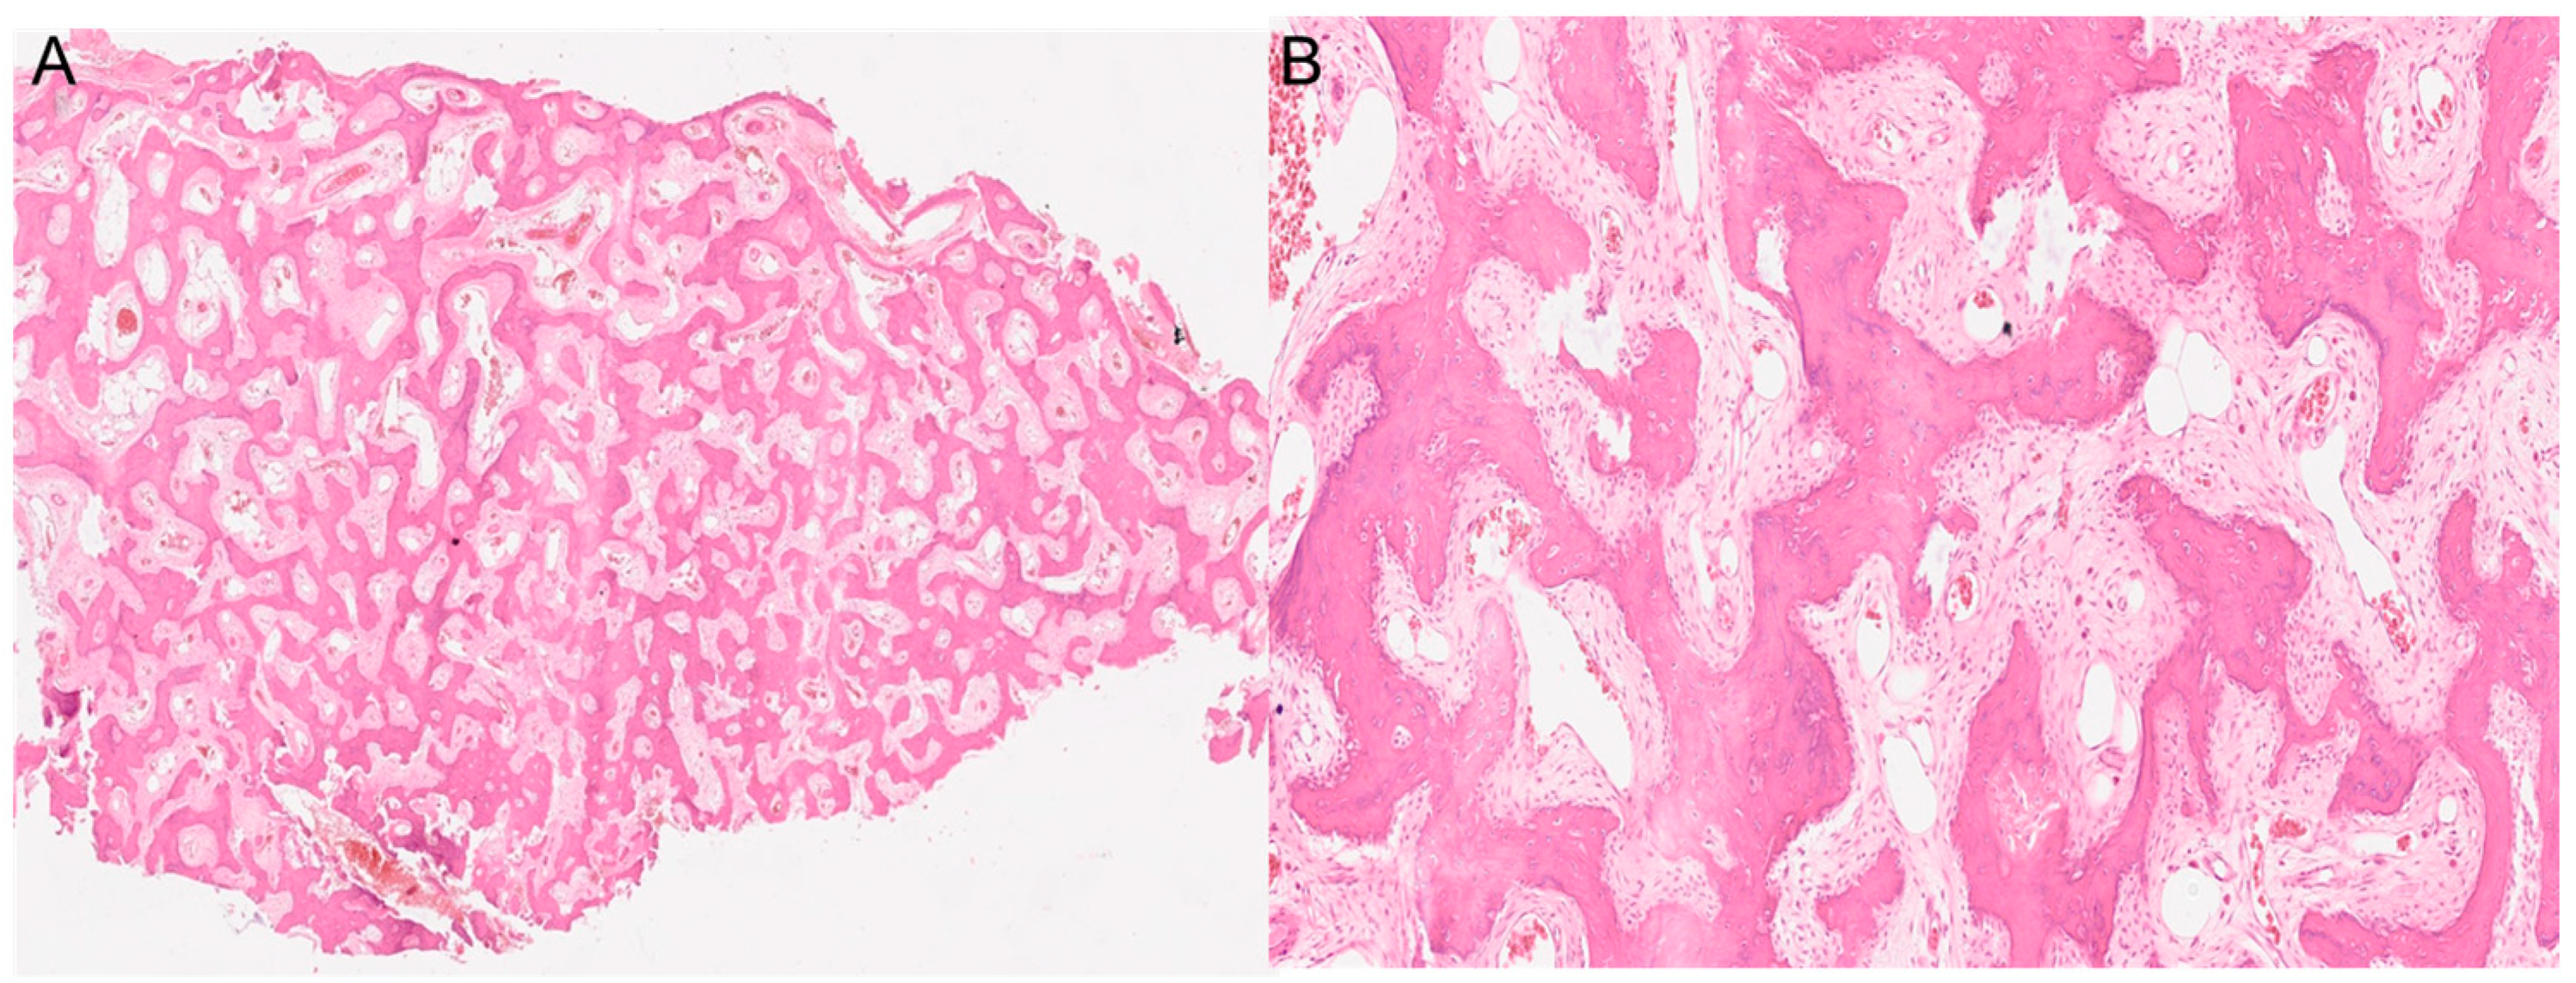

Both histological reports confirmed the diagnosis of fibrous dysplasia, showing a bone-fibrous fragment including bone trabeculae with irregular distribution with a crossed fibers structure with marked remodeling, and a non-atypic fibrous tissue with several vascular structures with thick and mineralized walls (Figure 3).

Figure 3.

The histopathological images show a section of the middle turbinate. (A) 4× magnification. (B) 20× magnification. Both images show the main characteristics of fibrous dysplasia, such as fibrous tissue intermixed with irregularly distributed bony trabeculae.

Moreover, in continuity with this tissue, they showed a de-epithelialized mucosa with normal gland structures. The Ki67 expression shown was <5%.